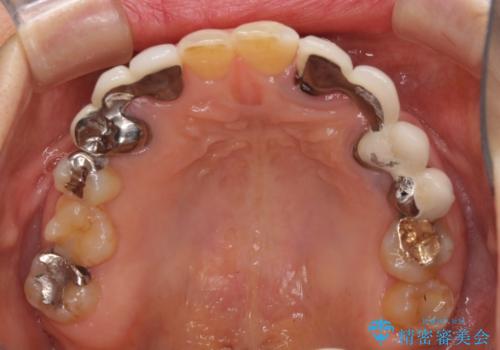

- 割れていると言われて放置してしまった歯や、前歯のデコボコなどが気になるとのことで来院された患者様です。

左上の歯は割れてしまっており、抜歯のうえインプラント治療が必要であり、他にも抜歯の必要な歯がある状態でした。

上顎はほぼ全ての歯をセラミッククラウンにて補綴治療を行う必要があるため、気になるデコボコや深い咬み合わせを改善するために下顎と上顎の臼歯部の矯正治療を行うこととしました。

並行して左下にはインプラントを埋入し、矯正治療を終えると同時に補綴治療を行うこととしました。